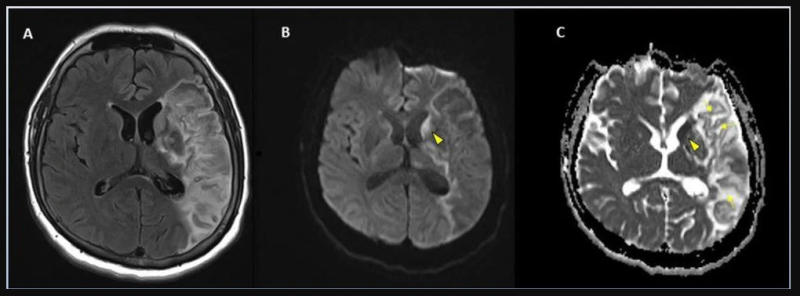

This photo gallery shows the variety of radiological presentations of COVID-19 (SARS-CoV-2) in medical imaging, including computed tomography (CT), radiograph X-rays, ultrasound, echocardiograms and magnetic resonance imaging (MRI). The radiology images show examples of typical COVID pneumonia in the lungs and the numerous complications the virus causes in the body in multiple organs, including the brain, kidneys, heart, abdomen and vascular system.

The images were collected from physicians, study authors, universities and hospitals, the National Institutes of Health (NIH), the Radiological Society of North America (RSNA), the American College of Radiology (ACR), Centers for Disease Control and Prevention (CDC) and radiology technology vendors.